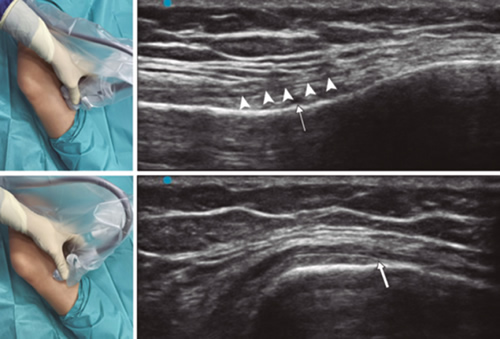

Para lograr una correcta ubicación de las referencias anatómicas por ultrasonido debemos colocar al paciente en posición supina con la rodilla flexionada y una almohada debajo de la fosa poplítea (14,16,19). Después de realizar asepsia/antisepsia de la rodilla, colocación de campos quirúrgicos y de la funda estéril del transductor lineal de alta frecuencia, procedemos a ubicar el NGSM (Figura 3). Colocando la sonda en un plano coronal sobre la cara interna de la rodilla, la deslizamos en sentido craneal hasta visualizar la unión de la metáfisis con la diáfisis femoral y la arteria/nervio geniculado superomedial (ANGSM), usualmente están localizados cerca al periostio del fémur (en caso de no encontrar esta estructura neurovascular, se toma como referencia la unión de la metáfisis y la diáfisis femoral). Después se marca en la piel el punto medio del transductor que corresponde a la ANGSM y se gira el transductor para ubicarlo en el plano transversal o axial para visualizar la ANGSM en eje corto (si no es posible la visualización de esta estructura, confirmar que estamos a un 50 % de la profundidad del fémur). En este corte transversal se avanza la aguja de RFT en plano desde anterior a posterior hacia la ANGSM o hasta una profundidad del 50 % del espesor del fémur. Finalmente se vuelve a girar el transductor 90°, dejándolo en un plano coronal para comprobar que la punta de la aguja está cerca de la ANGSM o de la unión de la metáfisis y la diáfisis femoral (14,16,19).

Fig. 3. Sonoanatomía y técnica para realizar el bloqueo del nervio geniculado superomedial (NGSM). El transductor se ubica en el eje largo distal del fémur y una vez que se tenga la posición del NGSM (asteriscos), se gira la sonda 90 grados para obtener una visión en eje corto del fémur (no olvidar mantener la misma profundidad a la que encontramos el NGSM en el eje largo). VM: vasto medial.

Para ubicar al NGIM (Figura 4) colocamos el transductor en un plano coronal sobre la cara interna de la rodilla, lo deslizamos en sentido caudal hasta identificar la unión de diáfisis con la metáfisis tibial y la arteria/nervio geniculado inferomedial (ANGIM), y repetimos los mismos pasos que usamos para el NGSM. En caso de no encontrar la ANGIM, la referencia que se tomará será la profundidad del 50 % del espesor de la tibia (14,16,19).

Fig. 4. Sonoanatomía y técnica para realizar el bloqueo del nervio geniculado inferomedial (NGIM). El transductor se ubica en el eje largo proximal de la tibia e identificamos el paquete vasculonervioso del NGIM (flecha) justo debajo ligamento colateral medial (puntas de flechas). Luego se gira la sonda 90 grados para obtener una visión en eje corto de la tibia (no olvidar mantener la misma profundidad a la que encontramos el NGIM en el eje largo).